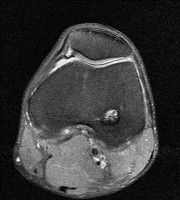

무릎 mri 간단히 봐주실 수 있으시나요 ㅠㅠ

안녕하세요 8년전 십자인대 수술하고 최근 무리한 운동에 무릎 불편감이 생겨서

mri 찍었습니다.

진단결과는 첫 찍은 병원에서 활액막염 이라는 진단을 받았습니다. 혹시 봐주실 수 있으실까요?

올라온 MRI가 단편적이라서 정확한 진단에 어려움이 있지만 십자인대에는 큰 이상이 있지는 않은것 같으며, 무릎관절내 물이 있는 것으로 보아 활액막염의 진단이 맞을 것 같습니다.

하지만 단편적인 영상이기 때문에 촬영병원에서 정확한 판독지 등을 받으시는 것이 좋겠습니다.